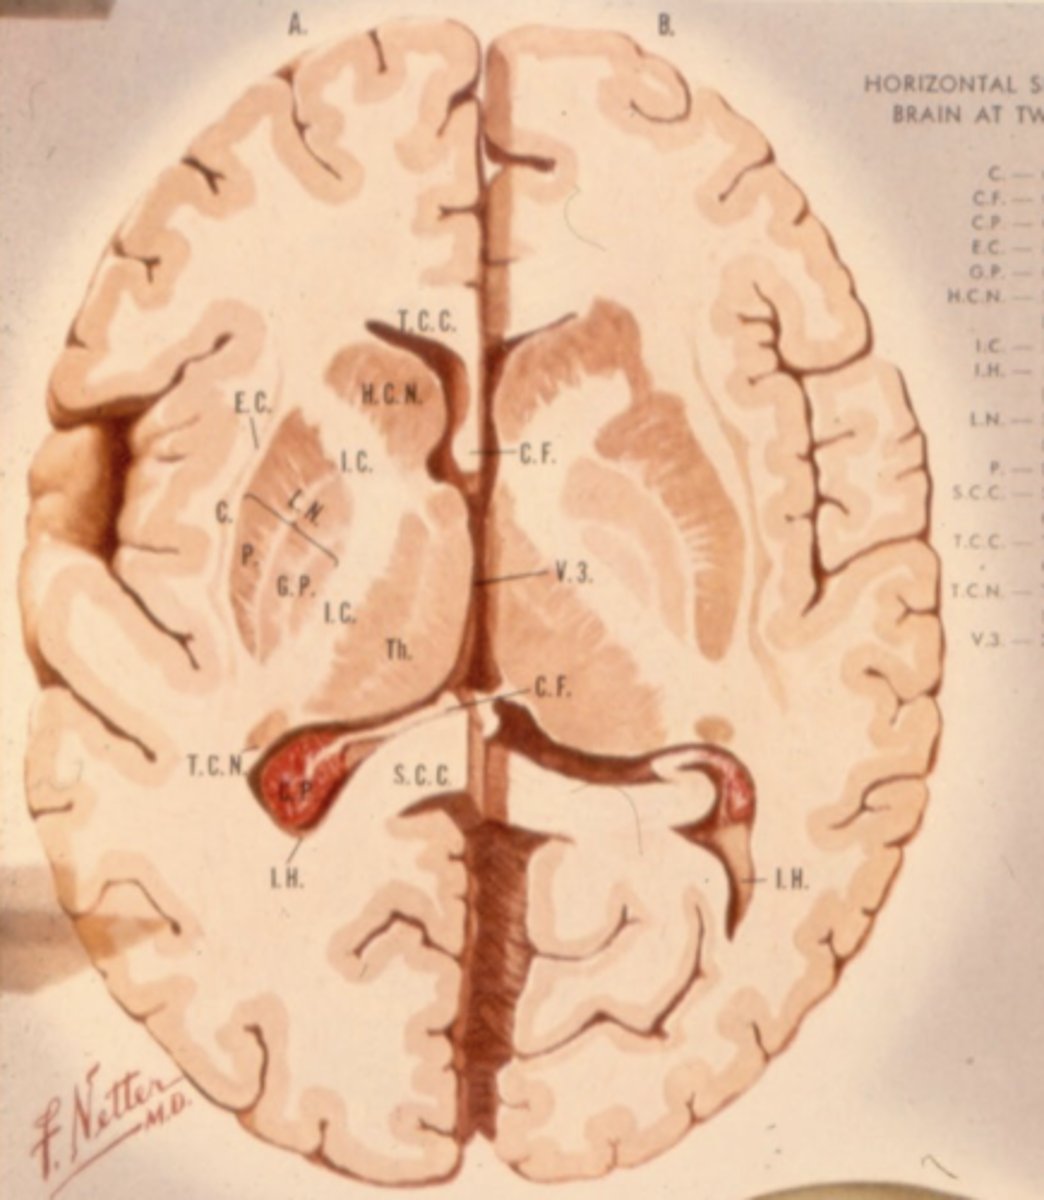

What is lateral to the thalamus?

posterior limb of internal capsule

What are the three nuclear complexes of the thalamus?

1. anterior nuclei

2. medial nuclei (connected by massa intermedia)

3. lateral nuclei

What are the nuclei (discussed) of the lateral nuclei of the thalamus?

1. LGN

2. MGN

3. pulvinar

4. VPL

5. VPM

What are the nuclei (discussed) of the lateral nucleus of the thalamus?

1. LGN

2. MGN

3. VPL (ventral posterolateral nucleus)

4. VPM (ventral posteromedial nucleus)

5. pulvinar